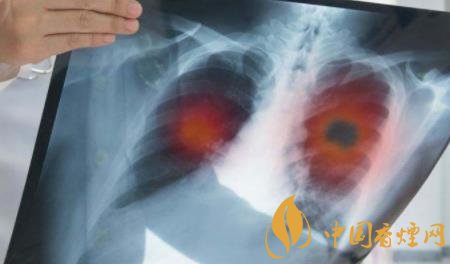

2、長期吸煙危害肺部健康

吸煙會(huì)產(chǎn)生大量的煙霧,而這些煙霧中含有大量的有害物質(zhì),如焦油、尼古丁、一氧化碳等成分,每當(dāng)你抽煙的時(shí)候,這些毒素就會(huì)隨著煙霧進(jìn)入到肺部,如果長時(shí)間抽煙的話,這些毒素就會(huì)在肺部里積便越來越多,會(huì)打破肺部功能的自身紊亂,使肺部無法正常的活動(dòng),會(huì)引發(fā)很多肺部疾病。

5、長期抽煙也容易誘發(fā)癌癥

香煙中含有大量的尼古丁、一氧化碳等都是誘發(fā)癌癥的高危物質(zhì),長期抽煙會(huì)使患發(fā)癌癥的幾率嚴(yán)重升高,從而引發(fā)癌癥的風(fēng)險(xiǎn),加大死亡的概率。